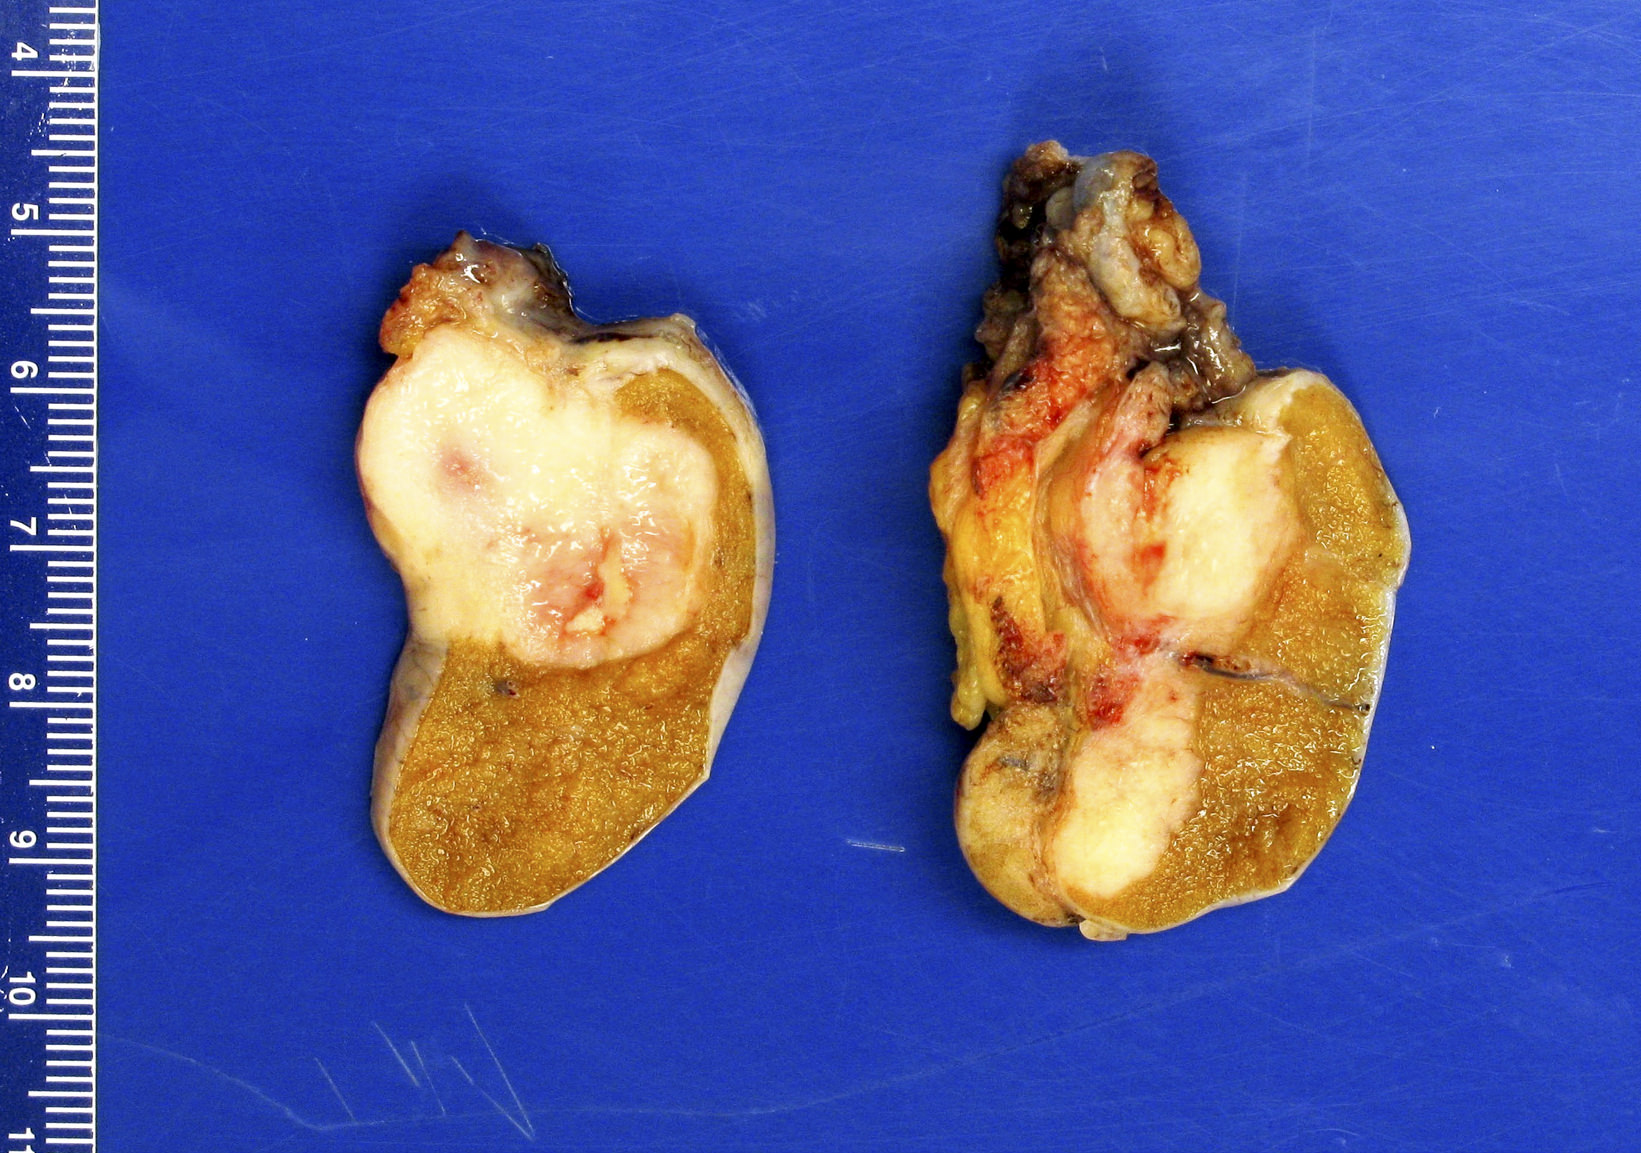

Gross images

Contributed by Debra L. Zynger, M.D.

Seminoma (pT1a)

Seminoma (pT1b)

Mixed germ cell tumor (pT2)

Seminoma (pT2)